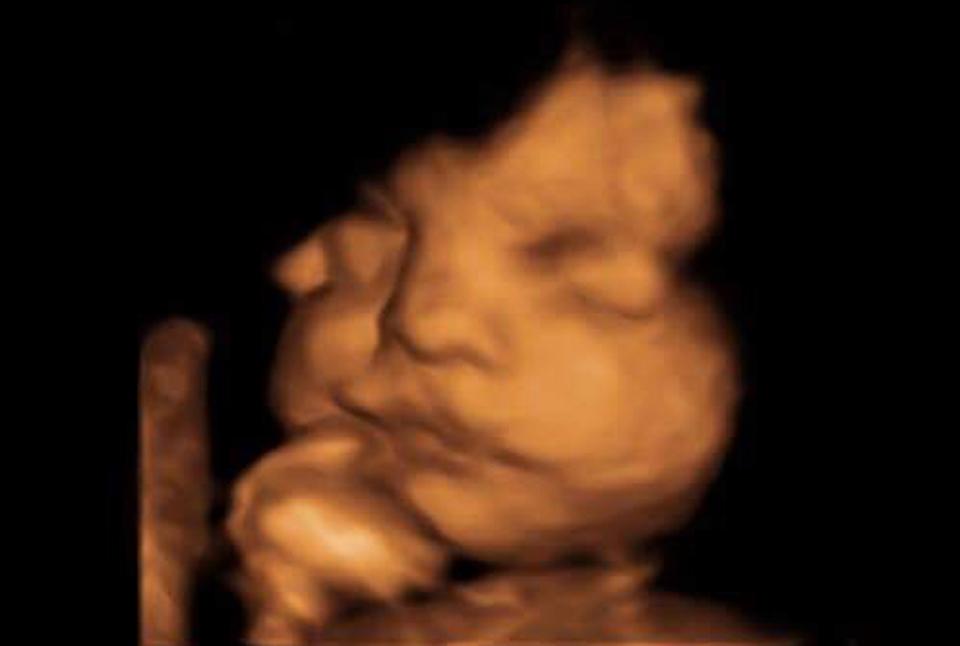

Cặp vợ chồng trẻ Lucy Bearley và Stuart Barrett đến từ Thatcham, Berkshire, Anh, đã có một trải nghiệm không thể quên với đứa con sắp chào đời. Khi thai nhi ở tuần tuổi 28, Lucy quyết định đi siêu âm tại một phòng khám ở Newbury. Quá trình siêu âm vẫn diễn ra bình thường cho đến khi em bé dường như quay đầu lại và vẫy tay với mọi người.

Em bé được dự kiến sinh vào ngày 5/3 tới đây. Đây là lần đầu tiên Lucy mang thai nên khoảnh khắc này vô cùng quý giá đối với cô. “Ban đầu tôi không mấy bận tâm, cho đến khi Stuart nói anh ấy thấy con chúng tôi vẫy tay chào. Tôi yêu cầu y tá quay lại đoạn phim để có thể nhìn kĩ hơn. May mắn là cô ấy đã bắt đúng khoảnh khắc thiêng liêng, thiên thần nhỏ không những chào mà còn quay sang nhìn chúng tôi nữa”, Lucy hạnh phúc nói.